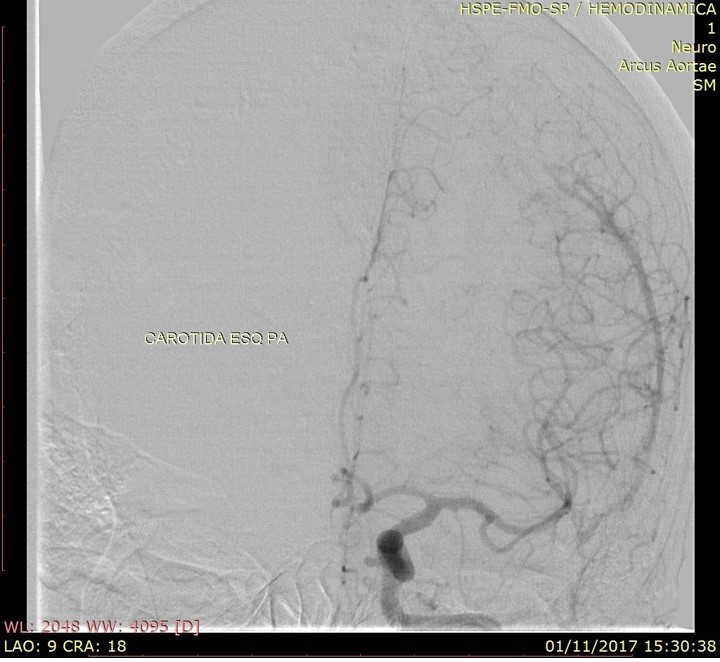

Discussão de tratamento de Fístula Arteriovenosa Dural grau I

Malformações artério venosas durais intracranianas - Discussão de caso fístula dural pós traumática grau I

Fístulas arteriovenosas durais (FAVDs) são lesões adquiridas, que consistem em uma ou mais conexões fistulosas no interior dos folhetos da dura-máter, envolvendo mais especificamente as paredes de um seio venoso dural ou as veias leptomeníngeas adjacentes.

Em 1995, Cognard et al. analisaram retrospectivamente 205 pacientes portadores de FAVDs, atendidos no período de 18 anos, em três grandes centros de referência no mundo. Algumas alterações e complementações foram propostas à classificação estabelecida anteriormente por Djindjian et al.  Na classificação publicada por Cognard et al., as lesões tipo I possuem drenagem diretamente para o interior de um seiovenoso dural, somente de forma anterógrada . As lesões tipo II são caracterizadas por elevada sobrecarga arterial e insuficiente drenagem venosa anterógrada. Ocorre, então, fluxo retrógrado ao longo do seio venoso.  Essa categoria é subdividida em três grupos,incluindo: tipo lIa com fluxo retrógrado somente no interior do seio venoso; tipo Ilb, com fluxo anterógrado no interior do seio venoso e refluxo para as veias corticais; e tipo lIa + b, com fluxo retrógrado para o seio e veias corticais. As lesões tipo III drenam exclusivamente para as veias corticais sem ectasia venosa. As lesões tipo IV drenam diretamente para as veias corticais que possuem ectasia venosa (dilatação maior que 5 mm de diâmetro). Finalmente, Cognard et al.acrescentaram um novo grupo, representado pelas lesões que drenam diretamente para as veias perimedulares espinhais, classificando-as como tipo V.